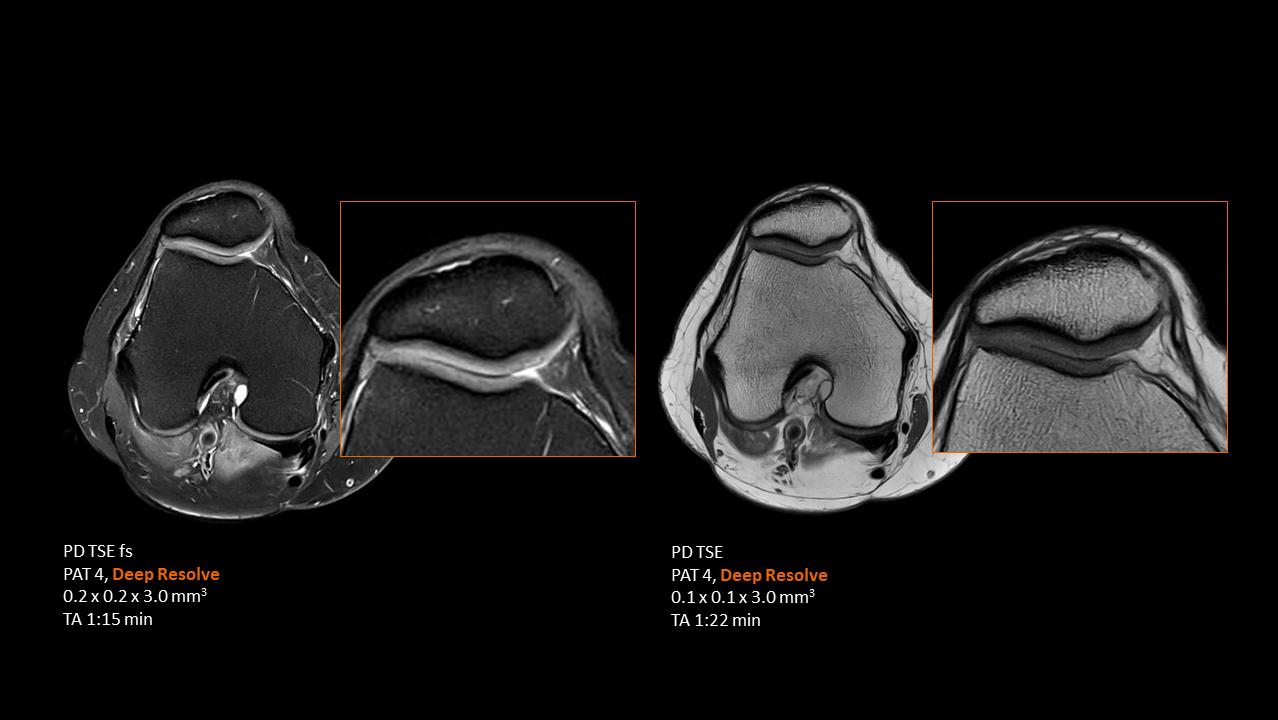

Deep Resolve will be at the forefront of the revolution in MRI acceleration. Deep Resolve will enable our fastest MRI, with images that will have extraordinary clarity, higher clinical productivity, and an even better patient experience. This transformational effect of Deep Resolve is now planned to expand to 3D5, unlocking a new dimension in MRI image resolution and speed.

More about Deep Resolve